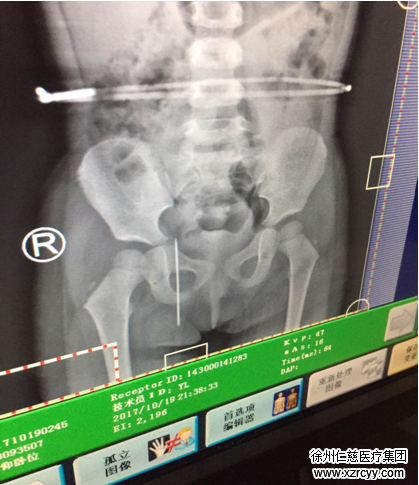

家住贾汪的欣欣今年2岁半,活泼可爱,聪明机灵。和其他小孩子不同的是:欣欣是一名留守儿童。早在欣欣7个月大还在嗷嗷待哺时,父母就前往深圳打工,欣欣一直由其爷爷奶奶照顾。昨天上午,欣欣奶奶在家缝补被子,补好被子上的一个洞,就把工具收了回去,却忘了床上那根又粗又长的缝被针。“当时我和她爷爷不在她身边,只知道她在床上看电视,也没喊没哭,到了晚上我看她走路一拐一拐的,就问她怎么回事,她也说不清楚,就说屁股痛。”眼见着欣欣闹腾着屁股痛,奶奶也急了,连夜带欣欣来到必威官方首页官网betway检查,结果令所有人都大吃一惊:X光显示欣欣的右臀处扎入了一根长约7厘米的缝被针!

betway在线登陆手外科一病区李甲主任介绍,诸如“绣花针、针灸针、缝被针”这类异物取出难度较高,因针体较细,在人体内的位置会不断“游离”。再者臀部脂肪和肌肉较多,更加难以取出,经过C型臂定位与反复探查,医生终于成功取出欣欣右臀里的缝被针。最后李甲主任提醒各位父母,锐利器物与各种对孩子有安全威胁的东西,家长一定要仔细收好!